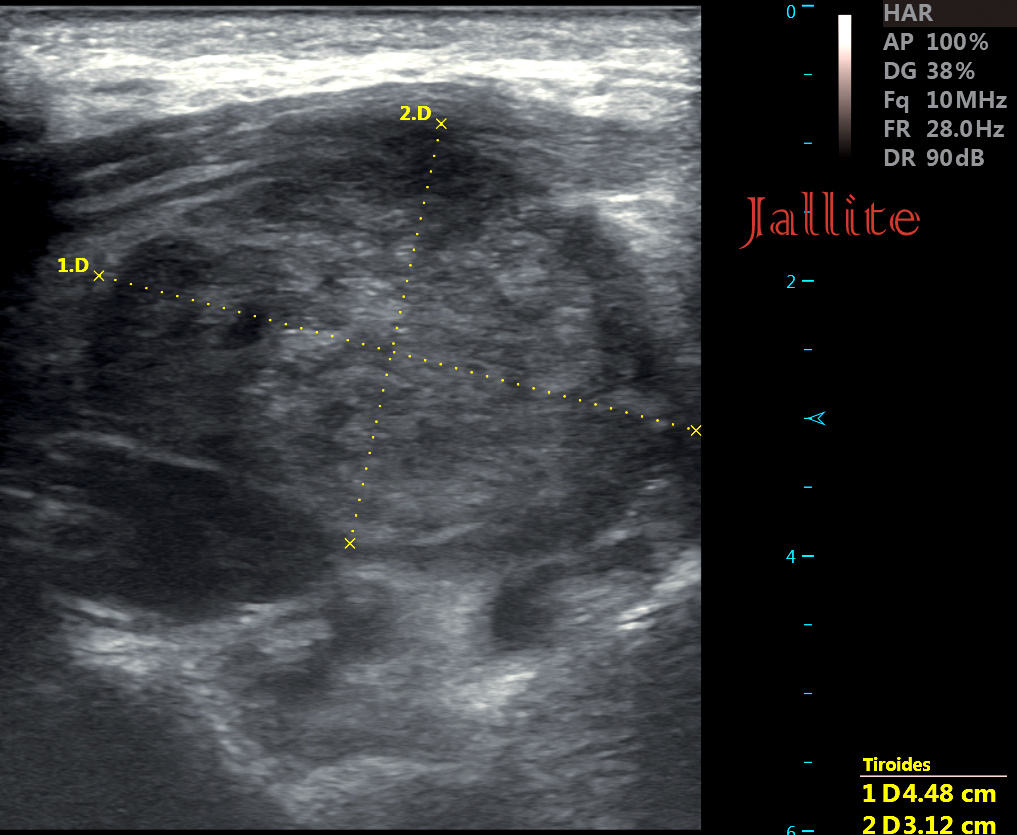

Los tumores del glomus carotídeo son lesiones de crecimiento lento, hipervascularizados, infrecuentes, derivados de células paraganglionares de la cresta neural y que representan casi la mitad de los paragangliomas.